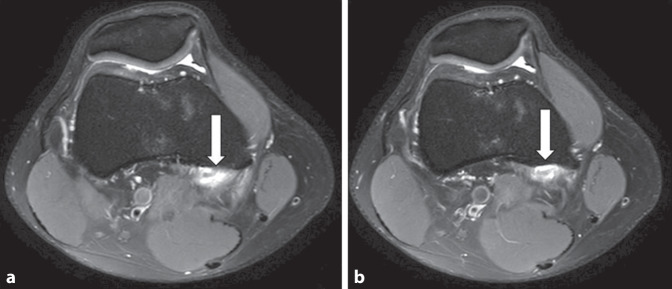

本病例报告介绍了一名32岁男性休闲运动员的临床表现和治疗方法,他表现为持续4个月的膝盖疼痛,没有外伤史。患者行走时间歇性疼痛,尤其是长时间坐着后,半月板检查呈阳性。然而,他能够毫无痛苦地参加体育活动。磁共振成像(MRI)显示腓肠肌内侧头部分撕裂,证实了诊断。保守治疗,包括休息、物理治疗和逐渐恢复体育活动,导致明显的症状改善。本病例强调了考虑罕见损伤的重要性,如腓肠肌内侧头的孤立撕裂,在持续的膝关节疼痛和半月板症状的患者中,即使没有创伤事件。先前关于这种特殊损伤的报道很少,表明其罕见性,并强调需要进一步了解和记录。

This case report presents the clinical findings and management of a 32-year-old male recreational athlete who presented with ongoing knee pain for 4 months, without a history of trauma. The patient experienced intermittent pain during walking, particularly after prolonged periods of sitting, and exhibited positive findings on meniscus tests. However, he was able to participate in sports activities without pain. Magnetic resonance imaging (MRI) revealed a partial tear of the medial gastrocnemius head, confirming the diagnosis. Conservative treatment, including rest, physical therapy, and a gradual return to sports activities, led to significant symptom improvement. This case highlights the importance of considering rare injuries, such as isolated tears of the medial gastrocnemius head, in patients with persistent knee pain and meniscal symptoms, even in the absence of traumatic events. Previous reports on this specific injury are sparse, indicating its rarity and underscoring the need for further understanding and documentation.